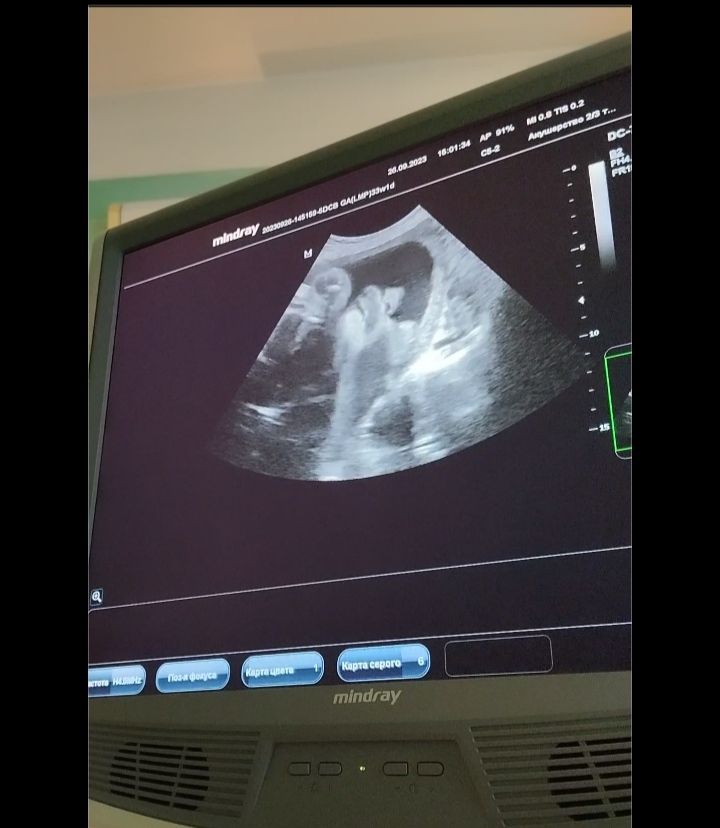

3е заключительное узи. Прошла!

Ну все, прошла сегодня последнее 3е УЗИ, все параметры в норме. Врач злая попалась, ничего особо не дала заснять, только мельком посмотрела своего мальчика) Личико пухленькие, носик ниже такой прикольный, мальчиковый)

Показали мужские причендалы, все на месте, ничего не отвалились, все также сын у меня на подходе)) Лежал во время УЗИ, губой нижней причмокивал😆

Ввела сейчас данные , и калькулятор показал абсолютно обычный вес 2215 гр, слава богу, не слоненок) Надеюсь сильно и не разростется к родам. Все-таки рожать лучше ребенка с нормальным весом чем раскормленного))

я ничего вообще не поняла. На снимке тоже ничего не видно))